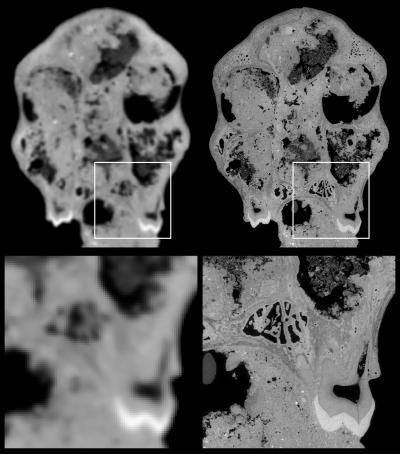

By examining the inner surface of the skull, the researchers hoped to recreate the shape and size of the brain. While the skull of the juvenile was originally examined with a medical CT scanner, the data did not allow detailed investigation of the internal structures, according to Carlson and colleagues.

The radiation produced from the beam is captured by straight beamlines that branch off of the ring. Fossils or other objects can be placed at the ends of these beamlines for imaging. Using a beamline at the ESRF, the group was able to scan the skull at a resolution (3D pixel size) of approximately 45 microns.

A comparison of the juvenile skull imaged with medical CT (left) versus synchrotron scanning (right). Voxel size is approximately 450 µm for the medical CT scan, compared with 45.71 µm with synchrotron imaging. Image courtesy of ESRF and Paul Tafforeau, PhD.Blocked by rock

"Imaging a partial hominum cranium filled with matrix and still achieving a resolution exceeding 100 µm (i.e., voxel size smaller than 50 µm) with phase contrast presented a considerable challenge," Carlson and colleagues wrote. Previously, synchrotron imaging had generally been limited to smaller fossils.